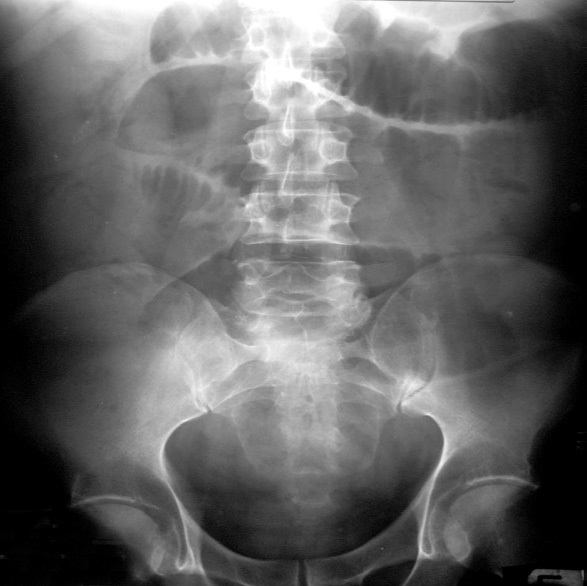

Erect x –ray abdomen:

Erect x-ray abdomen was done to look for free air under diaphragm and to look for obstruction